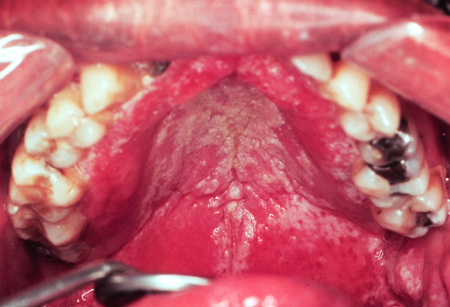

Candidíase oral

Candidíase oral (infecção oportunista) em um paciente infectado pelo vírus da imunodeficiência humana (HIV)

Public Health Image Library (PHIL)